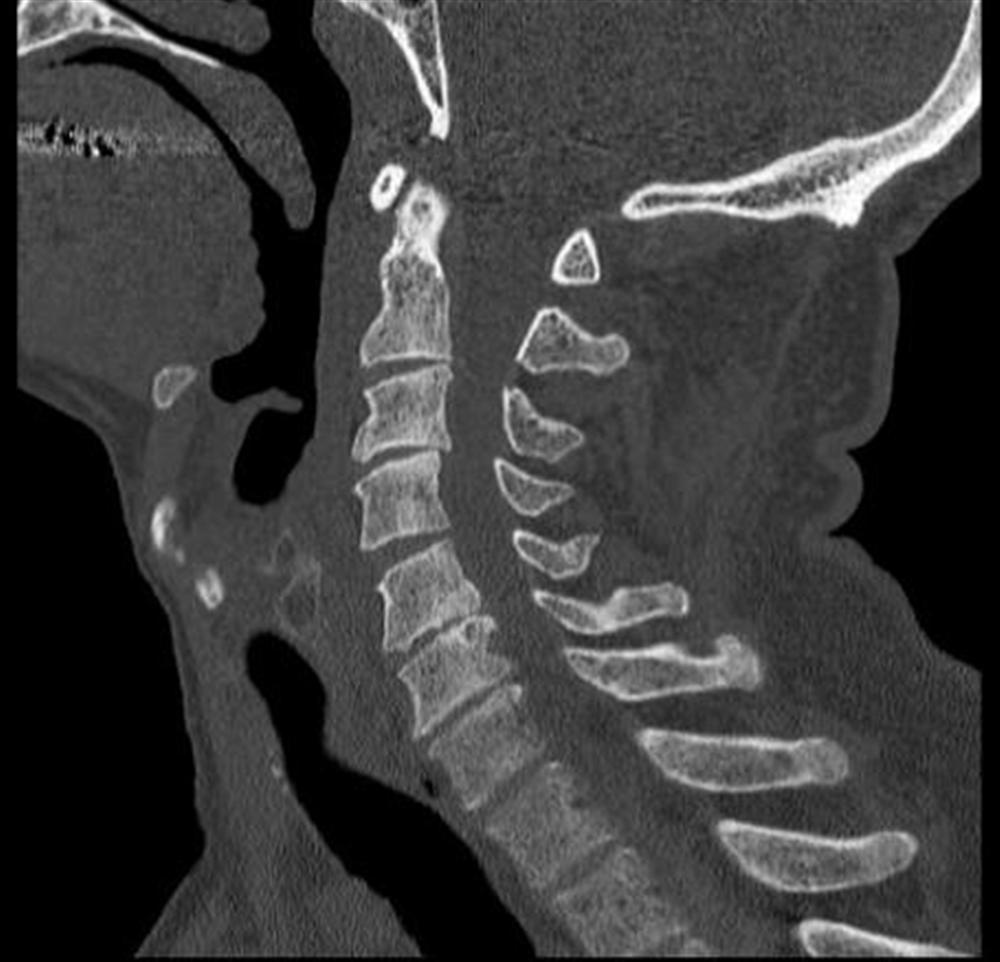

From www.orthobullets.com

Spinal Cord Injuries Spine Orthobullets Incomplete Spinal Cord Injury Physical Therapy Walking dysfunction is common in individuals with an incomplete spinal cord injury, arising not only from the impairments associated with the spinal. This affects the conduction of sensory and motor signals across the site. Defined as spinal cord injury with some preserved motor or sensory function below the injury level including: Spinal cord injury is defined as traumatic damage to. Incomplete Spinal Cord Injury Physical Therapy.